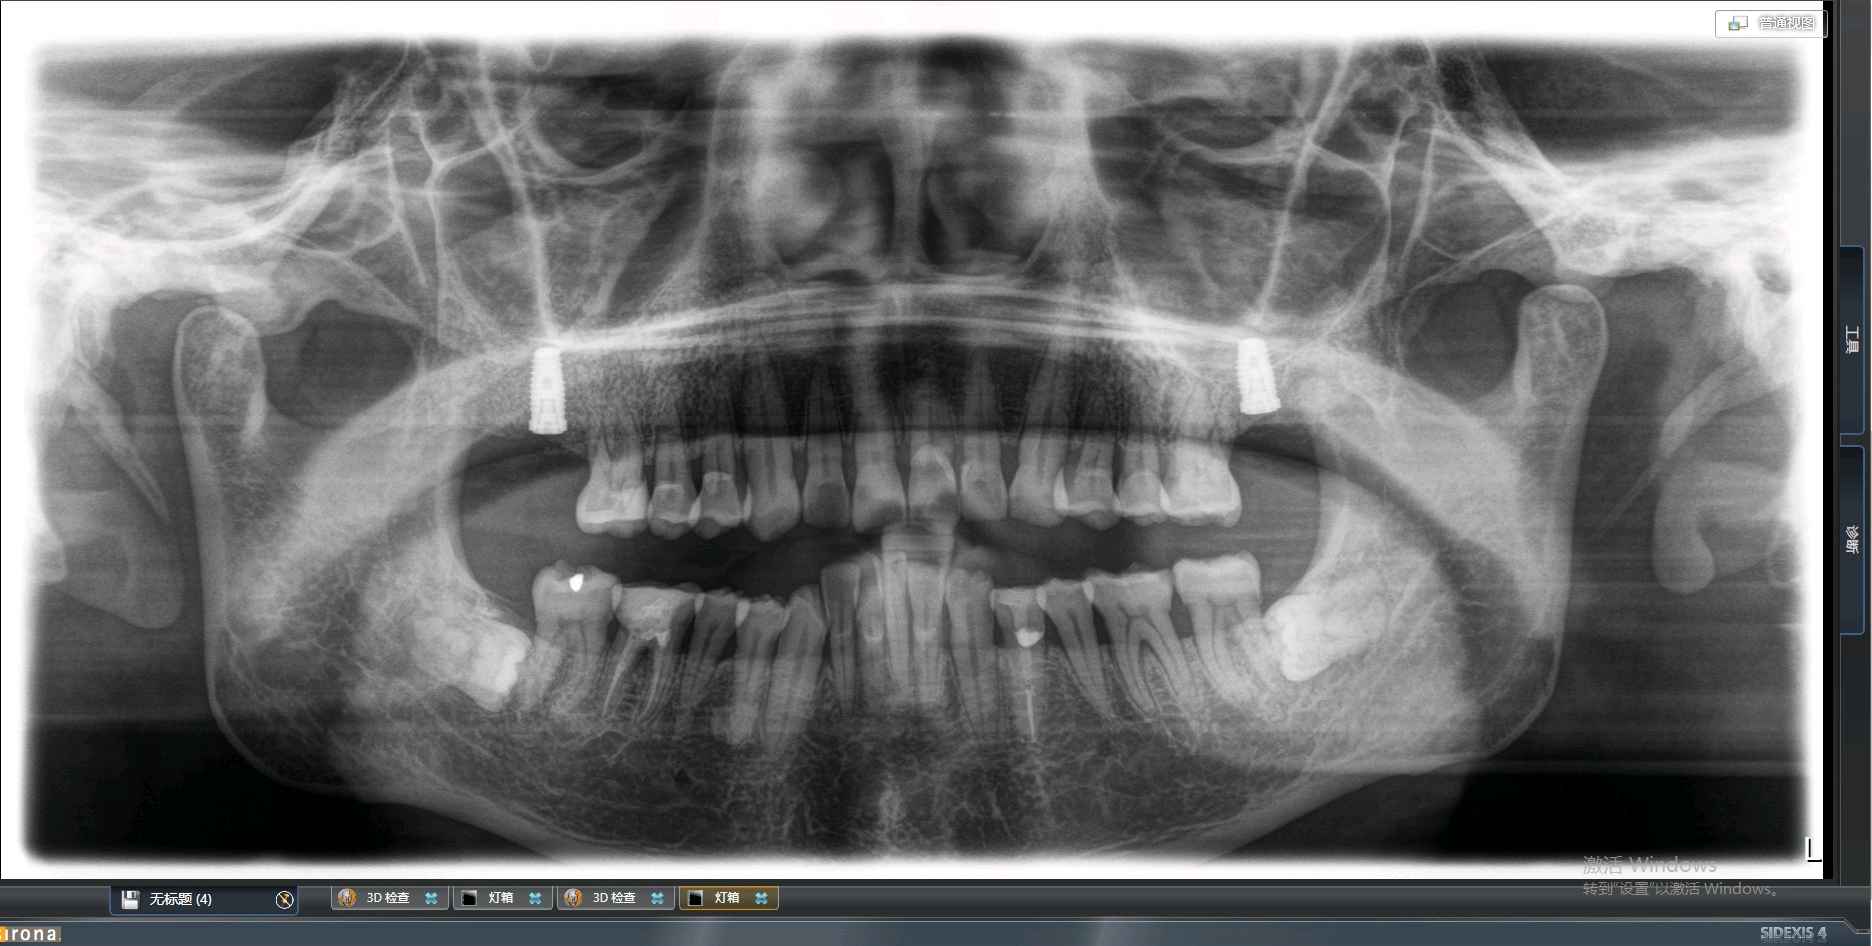

患者是成功人士,平时非常忙碌,忽略了口腔健康,直到有一天无法咀嚼食物后才想到要治疗牙齿,我们为他摄了CBCT,发现有重度牙周病,上合双侧7自然脱落,左上8,III度松动,并近中倾斜移位,对合牙严重伸长,还有其他牙齿疾患,需要综合治疗;经过牙周病治疗、上合窦骨增量、上合种植修复、拔牙、截冠、根管治疗、桩冠、高嵌体修复等!时间长达一年,终于恢复了正常牙列!可以享受食物的美好!